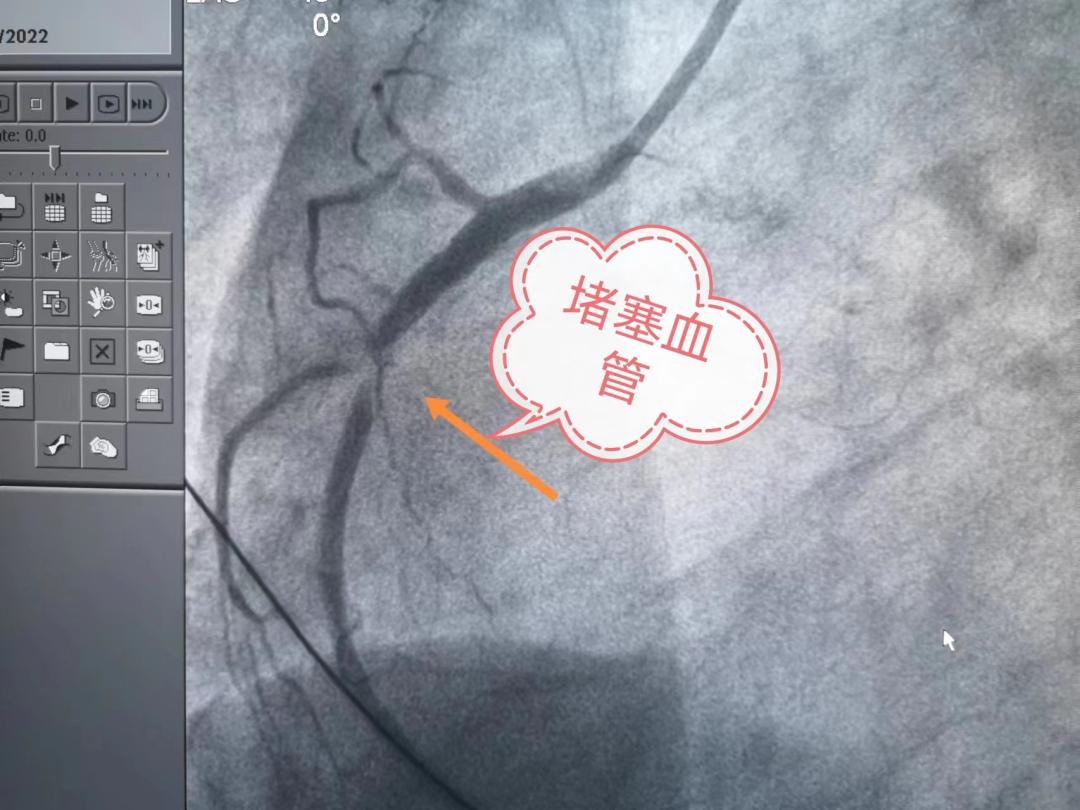

心血管堵塞造影图片

冠脉造影显示老杜的心脏血管多处堵塞,病变

行冠状动脉造影一看,所有人都惊出一身冷汗:心脏的两根重要血管完全

冠脉造影提示:左冠状动脉的前降支也有重度狭窄

第三例,造影见前降支次全闭塞

除颤后,送患者进入导管室,造影发现右侧血管近端99%狭窄,我们叫次全